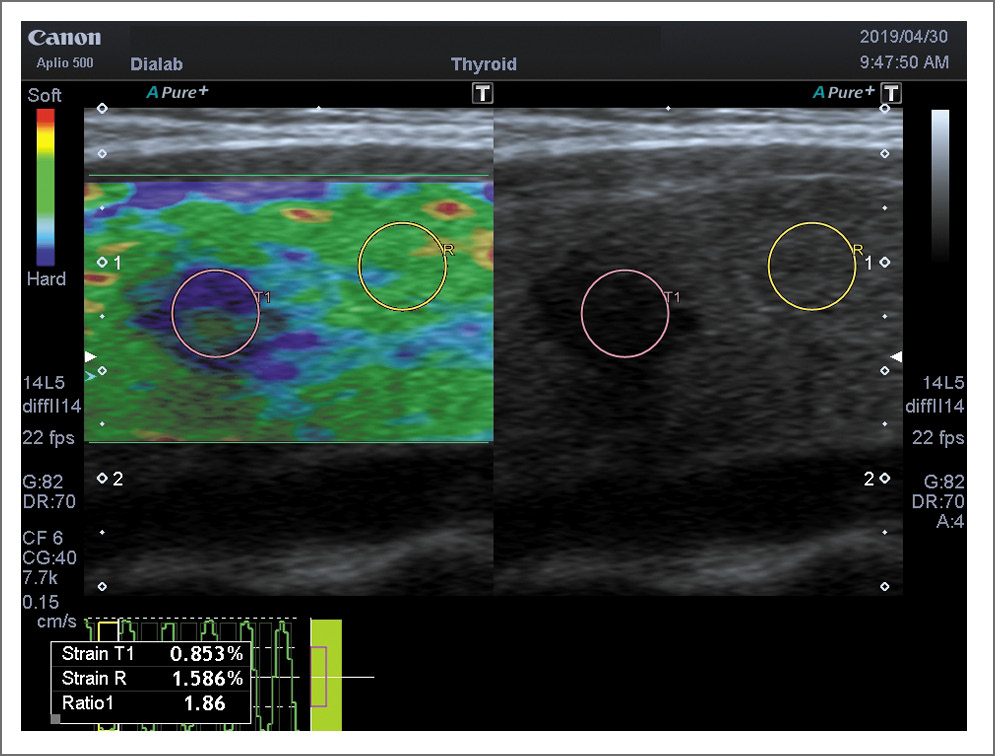

При определении качественных критериев по системе Tsukuba–Ueno большинство больных ПР отнесены к 3-му типу – 49 (65,3%): 3а – 10 (13,3%); 3б – 39 (52%). Тип 4 определен у 24 (32%), тип 5 – у 2 (2,7%) больных (рис. 3). В группе больных ПР на фоне АИТ преобладающее большинство отнесены к 3б типу – 14 (70%), 5 (25%) – к 4-му типу и 1 больной – ко 2-му типу (рис. 4).

Рис. 3. ПР. Компрессионная эластография, по системе Tsukuba–Ueno 4-й тип. Количественный показатель Strain Ratio – 1,86.

Рис. 4. ПР на фоне АИТ. Компрессионная эластография, по системе Tsukuba–Ueno 5-й тип (характерно для жестких тканей).